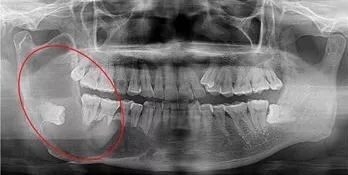

阻生牙(impacted teeth)是指部分萌出或完全不能萌出,且以后也不会自行萌出的牙。好发部位为下颌第三磨牙、上颌第三磨牙及上颌尖牙,其中阻生第三磨牙也叫做阻生智齿。

5、邻牙及支持组织的吸收:当阻生的智齿萌出过程中受阻于第二磨牙时,会引发第二磨牙牙根牙根逐渐吸收,严重者可使下颌第二磨牙远中牙根完全吸收,致第二磨牙松动、疼痛,常常食物嵌塞发生慢性牙周炎,也会造成牙槽骨的炎症性吸收,使第二磨牙反复肿痛。